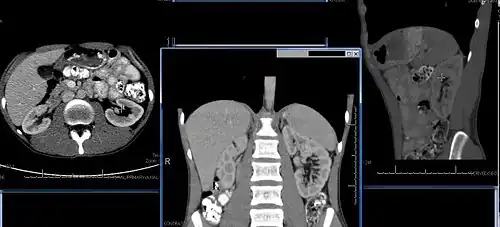

-

Normal adult right kidney as seen on abdominal ultrasound with a pole to pole measurement of 9.34 cm -

Imaging

Renal ultrasonography is essential in the diagnosis and management of kidney-related diseases.[49] Other modalities, such as CT and MRI, should always be considered as supplementary imaging modalities in the assessment of renal disease.[49]